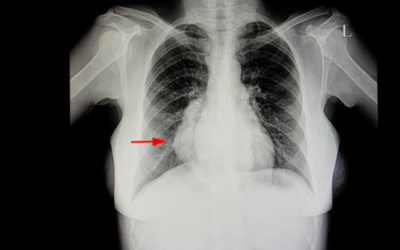

Lung Cancer

One of the primary concerns where a lung cancer specialist excises tumors, performs lobectomies, and segmental resections.

Latest Diagnostics

Including digital imaging (CT, MRI), cancer tumor markers, and endoscopy to ensure precision of diagnosis to the last detail.